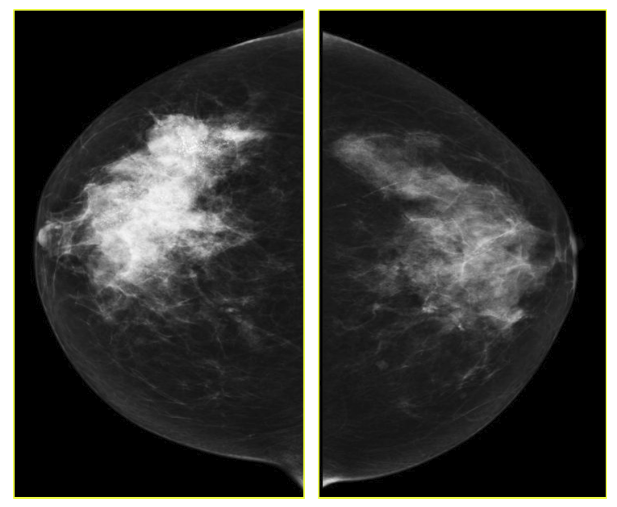

The goal of screening asymptomatic women is to find breast cancer in its earliest stages when treatment has the highest chance for survival. For diagnosis and characterization of primary breast lesions, anatomical imaging such as mammography is the most common screening test for breast cancer, which is basically an x-ray picture of the breast. Examples of mammography images are shown in Fig. 1 for a 67 year old patient. Mammography may find tumors that are too small to feel. It may also find ductal carcinoma in situ (DCIS) [10]. Mammography is more averse to discover breast tumors in women with dense breast tissue. Since both tumors and dense breast tissue seems white on a mammogram, it is hard to find a tumor when there is a dense breast tissue. The mammography sensitivity varies in the range depending on the age of the examined group and number. This range for sensitivity varies from 80% to 96% and in case of specificity it is in the range of 15 to 51.8% [11].